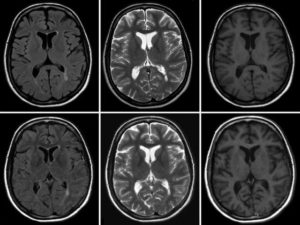

Для дегенеративных заболеваний головного мозга характерны атрофические изменения: ткани полушарий уменьшаются, борозды углубляются, а желудочки расширяются. Это наблюдается, например, при дисциркуляторной энцефалопатии. Также выявляются диффузные или локальные изменения в сером или белом веществе.

Рассеянный склероз имеет уникальную картину на МРТ: на сагиттальных срезах виден пунктир над третьим желудочком, служащий ранним признаком заболевания. Для рассеянного склероза также характерно образование пространств Вирхова-Робина — очаги нервной ткани с пониженной плотностью вокруг сосудов.

При рассеянном склерозе наблюдаются множественные гиперденсивные очаги.

МРТ головного мозга: рассеянный склероз, видны очаги демиелинизации

Рассеянный склероз.